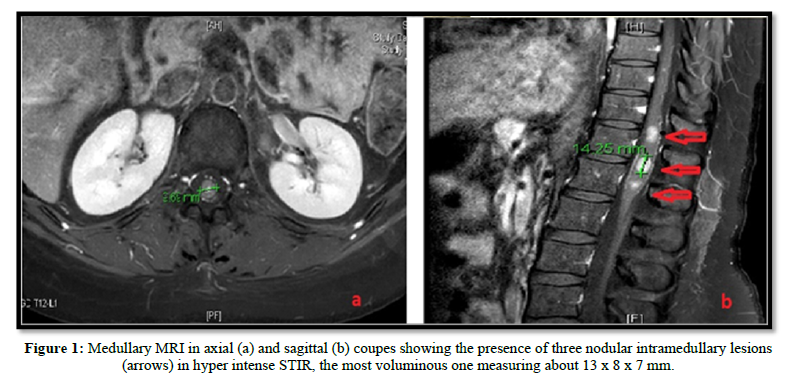

We report the case of a 35-year-old female patient, followed in Oncology-Radiotherapy department. Right breast biopsy revealed a grade 3 infiltrating ductal carcinoma. Hormonal receptors and Her-2 expression were found positive. Brain, liver and bones metastasis were detected at the time of diagnosis. She received brain radiotherapy (30 Gy) and then put under palliative oral chemotherapy associated with hormonotherapy with a good clinical outcome. Three months later, she developed neurological symptoms of medullary compression. The clinical examination found an incomplete left paraplegia with left leg anesthesia, right motor deficit (3/5). No sensory or sphincter disturbance were found and no pain symptoms. The MRI showed three nodular intra-medullary lesions localized at the terminal cone. The largest one was located on T12-L1, measuring 13 x 7 x 8 mm. The other two were located next to T12 and L1. The patient received high dose of corticosteroids and decompressive radiotherapy was performed with 30 Gy in 10 fractions of 3 Gy, improving initial symptoms. Another line of chemotherapy was recommended because metastatic disease progression (Figure 1).

the diagnosis is essentially based on medullary MRI which most often shows nodular lesions in the medullary canal in T1 hypo signal - T2 hyper signal and after injection of Gadolinium [6].